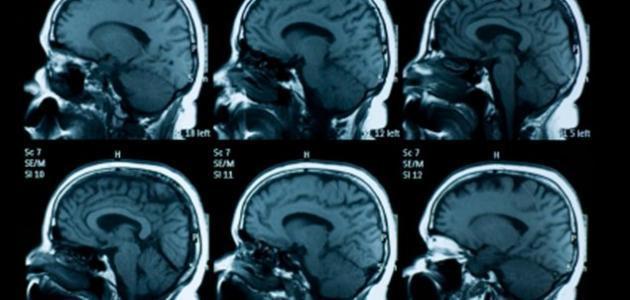

إن ضمور المخ هو حالة مرضية تسبب انكماش أجزاء من المخ أو المخ بشكل كامل عن طريق خسارة الخلايا بشكل تقدمي مع الوقت.